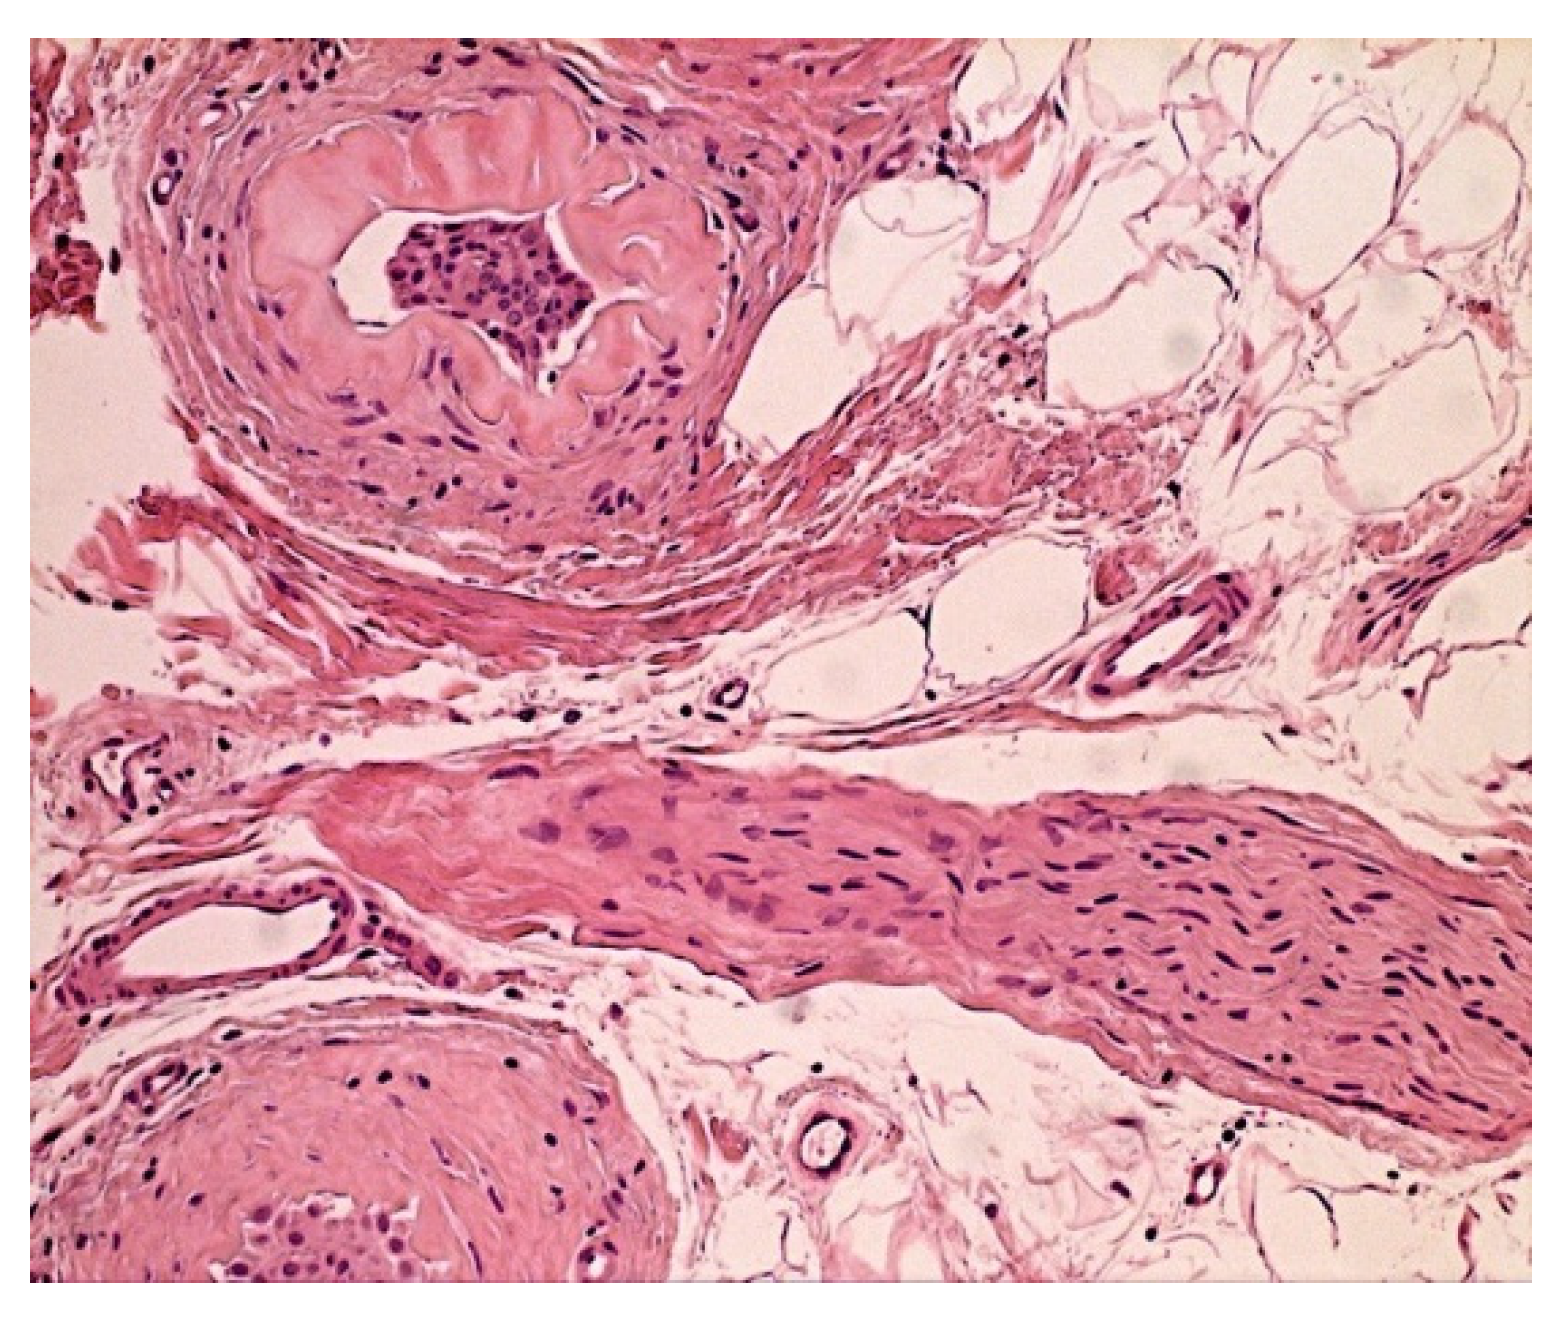

- Marušić, Z.; Korša, L.; Calonje, E. Dermal hyperneury. Clin. Dermatol. 2021, 39, 291–294. [Google Scholar] [CrossRef]

- Ieremia, E.; Marušić, Z.; Mudaliar, V.; Kelly, S.; Rodriguez, P.G.; McNiff, J.M.; LeBoit, P.E.; Calonje, E. Expanding the clinical spectrum of dermal hyperneury: Report of nine new cases and a review of the literature. Histopathology 2019, 75, 738–745. [Google Scholar] [CrossRef] [PubMed]